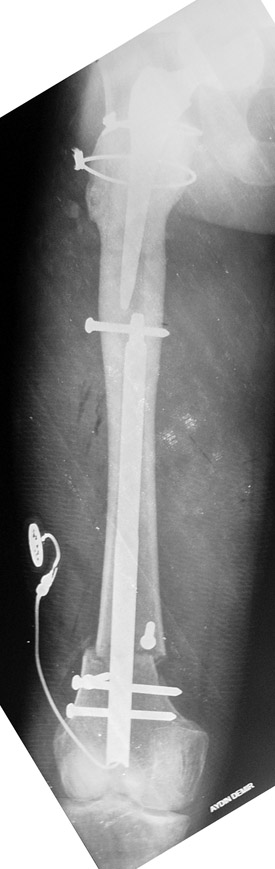

Vaka 1